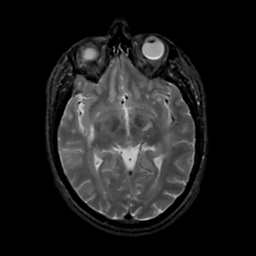

MR Study #16, June 23, 1991 -- Slice #23